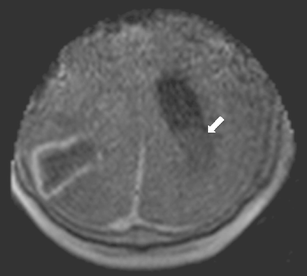

We performed an iMRI-guided surgical procedure in a patient with a cystic lesion of the inferior parieto-occipital lobe while the patient was placed in a semi-sitting position, employing a mobile 0.15-T intraoperative MRI system. For that purpose, we adapted a standard OR table according to the needs of iMRI.

Patient positioning could be accomplished easily. For intraoperative scanning, the OR table was tilted backwards so as to position the patient’s head in the magnet’s aperture. Obtained images were used for neuronavigated cyst evacuation via burr hole trephination after repositioning the OR table. Subsequent intraoperative imaging documented collapse of the cyst at the end of the procedure. There were no adverse effects resulting from the combination of semi-sitting position and iMRI guidance.